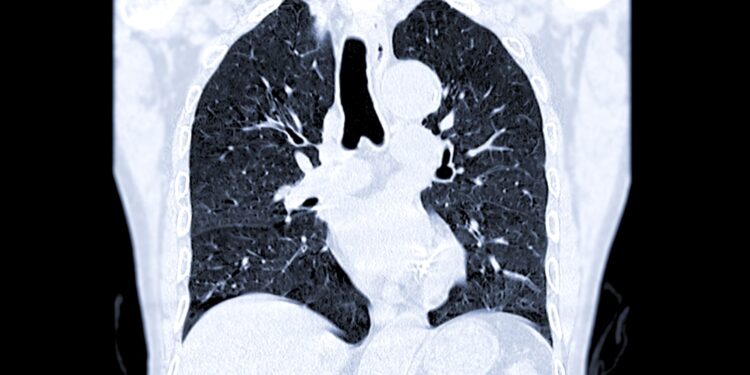

Dėl tam tikrų pokyčių nėštumo metu moters organizme kraujas kreša lengviau. Tai padidina tikimybę susidaryti giliųjų venų trombozei (GVT). Jos metu kraujo krešulys susiformuoja venoje, dažniausiai – vienoje ar abiejose kojose. Ištrūkęs trombas per kraujotaką gali nukeliauti į plaučius ir užkimšti ten esantį kraujagyslę. Tokia būklė vadinama plaučių embolija ir reikalauja skubios pagalbos.

Nustačius plaučių emboliją besilaukiančiai moteriai, paskiriamos specialios gydomosios injekcijos, stabdančios krešulio didėjimą ir leidžiančios organizmui jį pamažu ištirpinti. Dažniausiai vaistai vartojami iki nėštumo pabaigos ir papildomai dar šešias savaites po gimdymo, nes rizika išlieka ir šiuo laikotarpiu.